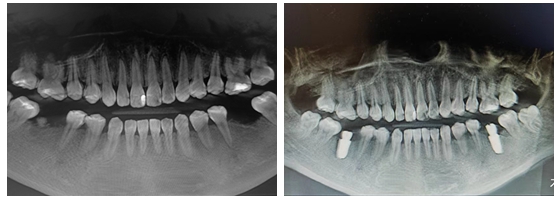

术前术后对比

7月3日下午,向峰主治医师在短短的40分钟内便为周女士顺利完成了2颗种植牙的植入,这也是洲口镇中心卫生院口腔科开展的首例种植手术。手术使用口腔局部麻醉系统进行无痛麻醉,待患者麻醉效果满意后,给予切开,翻瓣,扩孔到最后将种植牙植入牙槽骨内。全程微创,一气呵成,患者感受良好。术后,经口腔CBCT检查,种植体均得到了以“修复”为导向的植入。最终,周女士解除了对看牙的恐惧,连连道谢并说道:“市医疗资源向城乡基层下沉,让我们乡镇人民不出家门就可以享受高质量的医疗服务,确实是件好事情!”